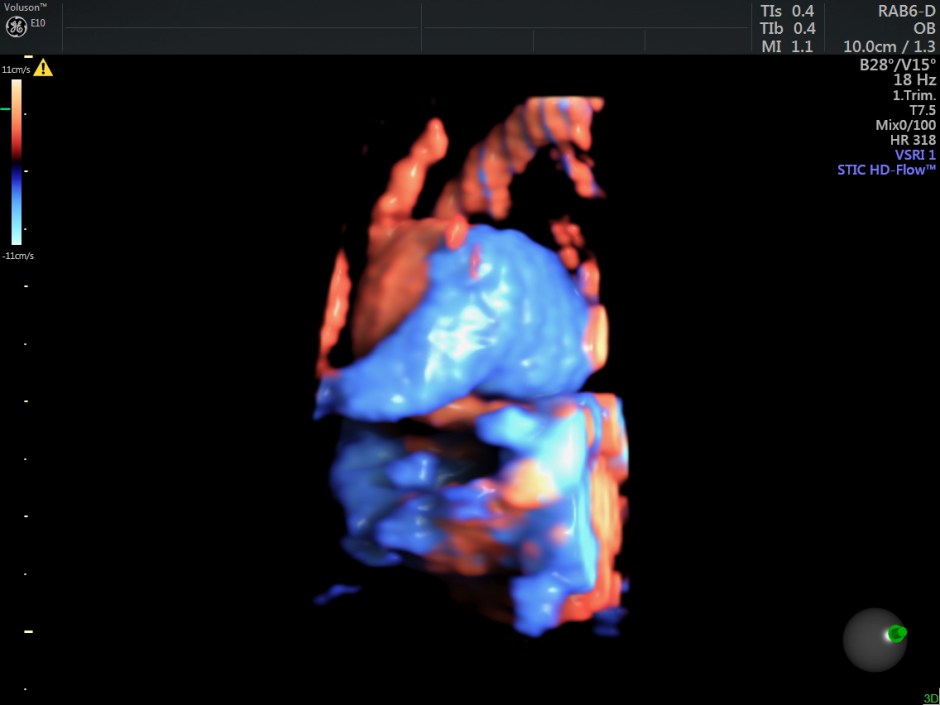

Reconstructed images show the feeding vessel and a vessel leaving the vascular structure.

STIC HIGH DEFINITION FLOW reconstruction images also show a feeding vessel and a vessel leaving the vascular structure,